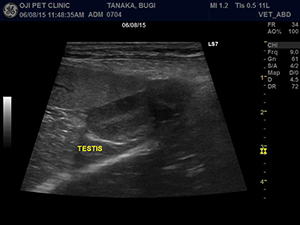

腹部超音波検査では脾臓の裏側に潜在精巣を確認しました。